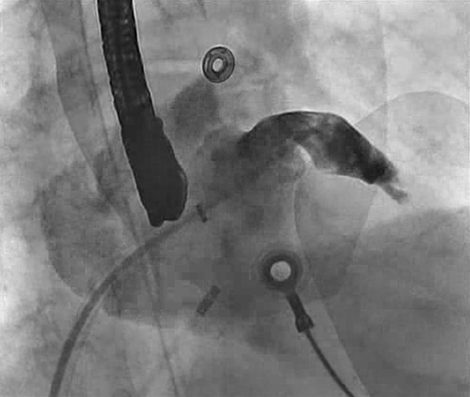

O Dr. Vivek Reddy realizou esse implante bem sucedido do Dispositivo WATCHMAN, assistido pelo Dr. Judy Hung e Dr. Andre D'Avila.

• Imagens TEE, ICE e fluoro foram usadas nesse caso.

Nesse caso ilustramos a caracterização adequada do apêndice atrial esquerdo, a medida do óstio e a posição correta do dispositivo WATCHMAN.